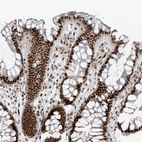

Immunohistochemical staining of human colon shows strong nuclear positivity in glandular cells.